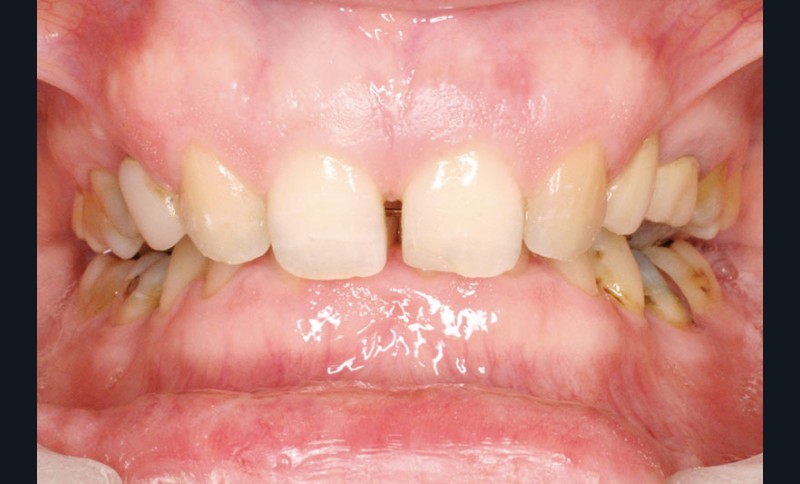

Un traitement orthodontique a déjà été effectué pendant son adolescence avec un choix de fermeture d’espaces qui a entraîné une linguoversion incisive maxillaire excessive (fig. 10), avec un préjudice esthétique important notamment sur le sourire (fig. 11 à 13).